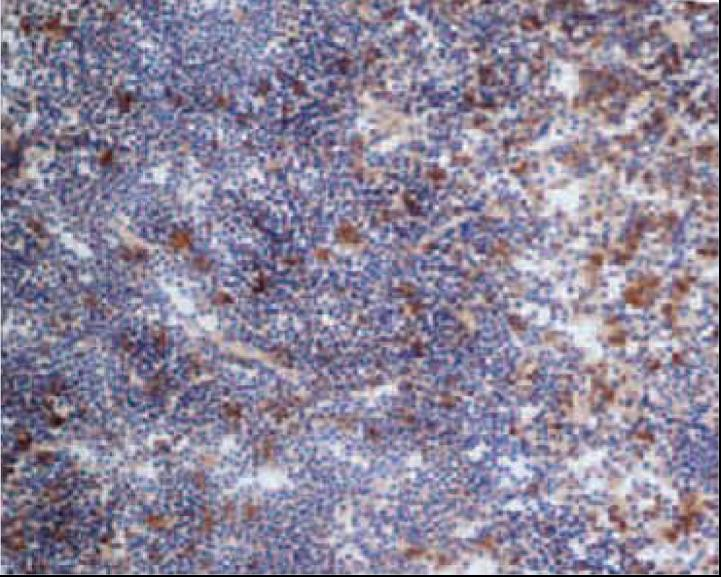

小鼠脾脏冰冻切片的免疫组化染色;红髓中的巨噬细胞用anti CD68(MCA1957)染色